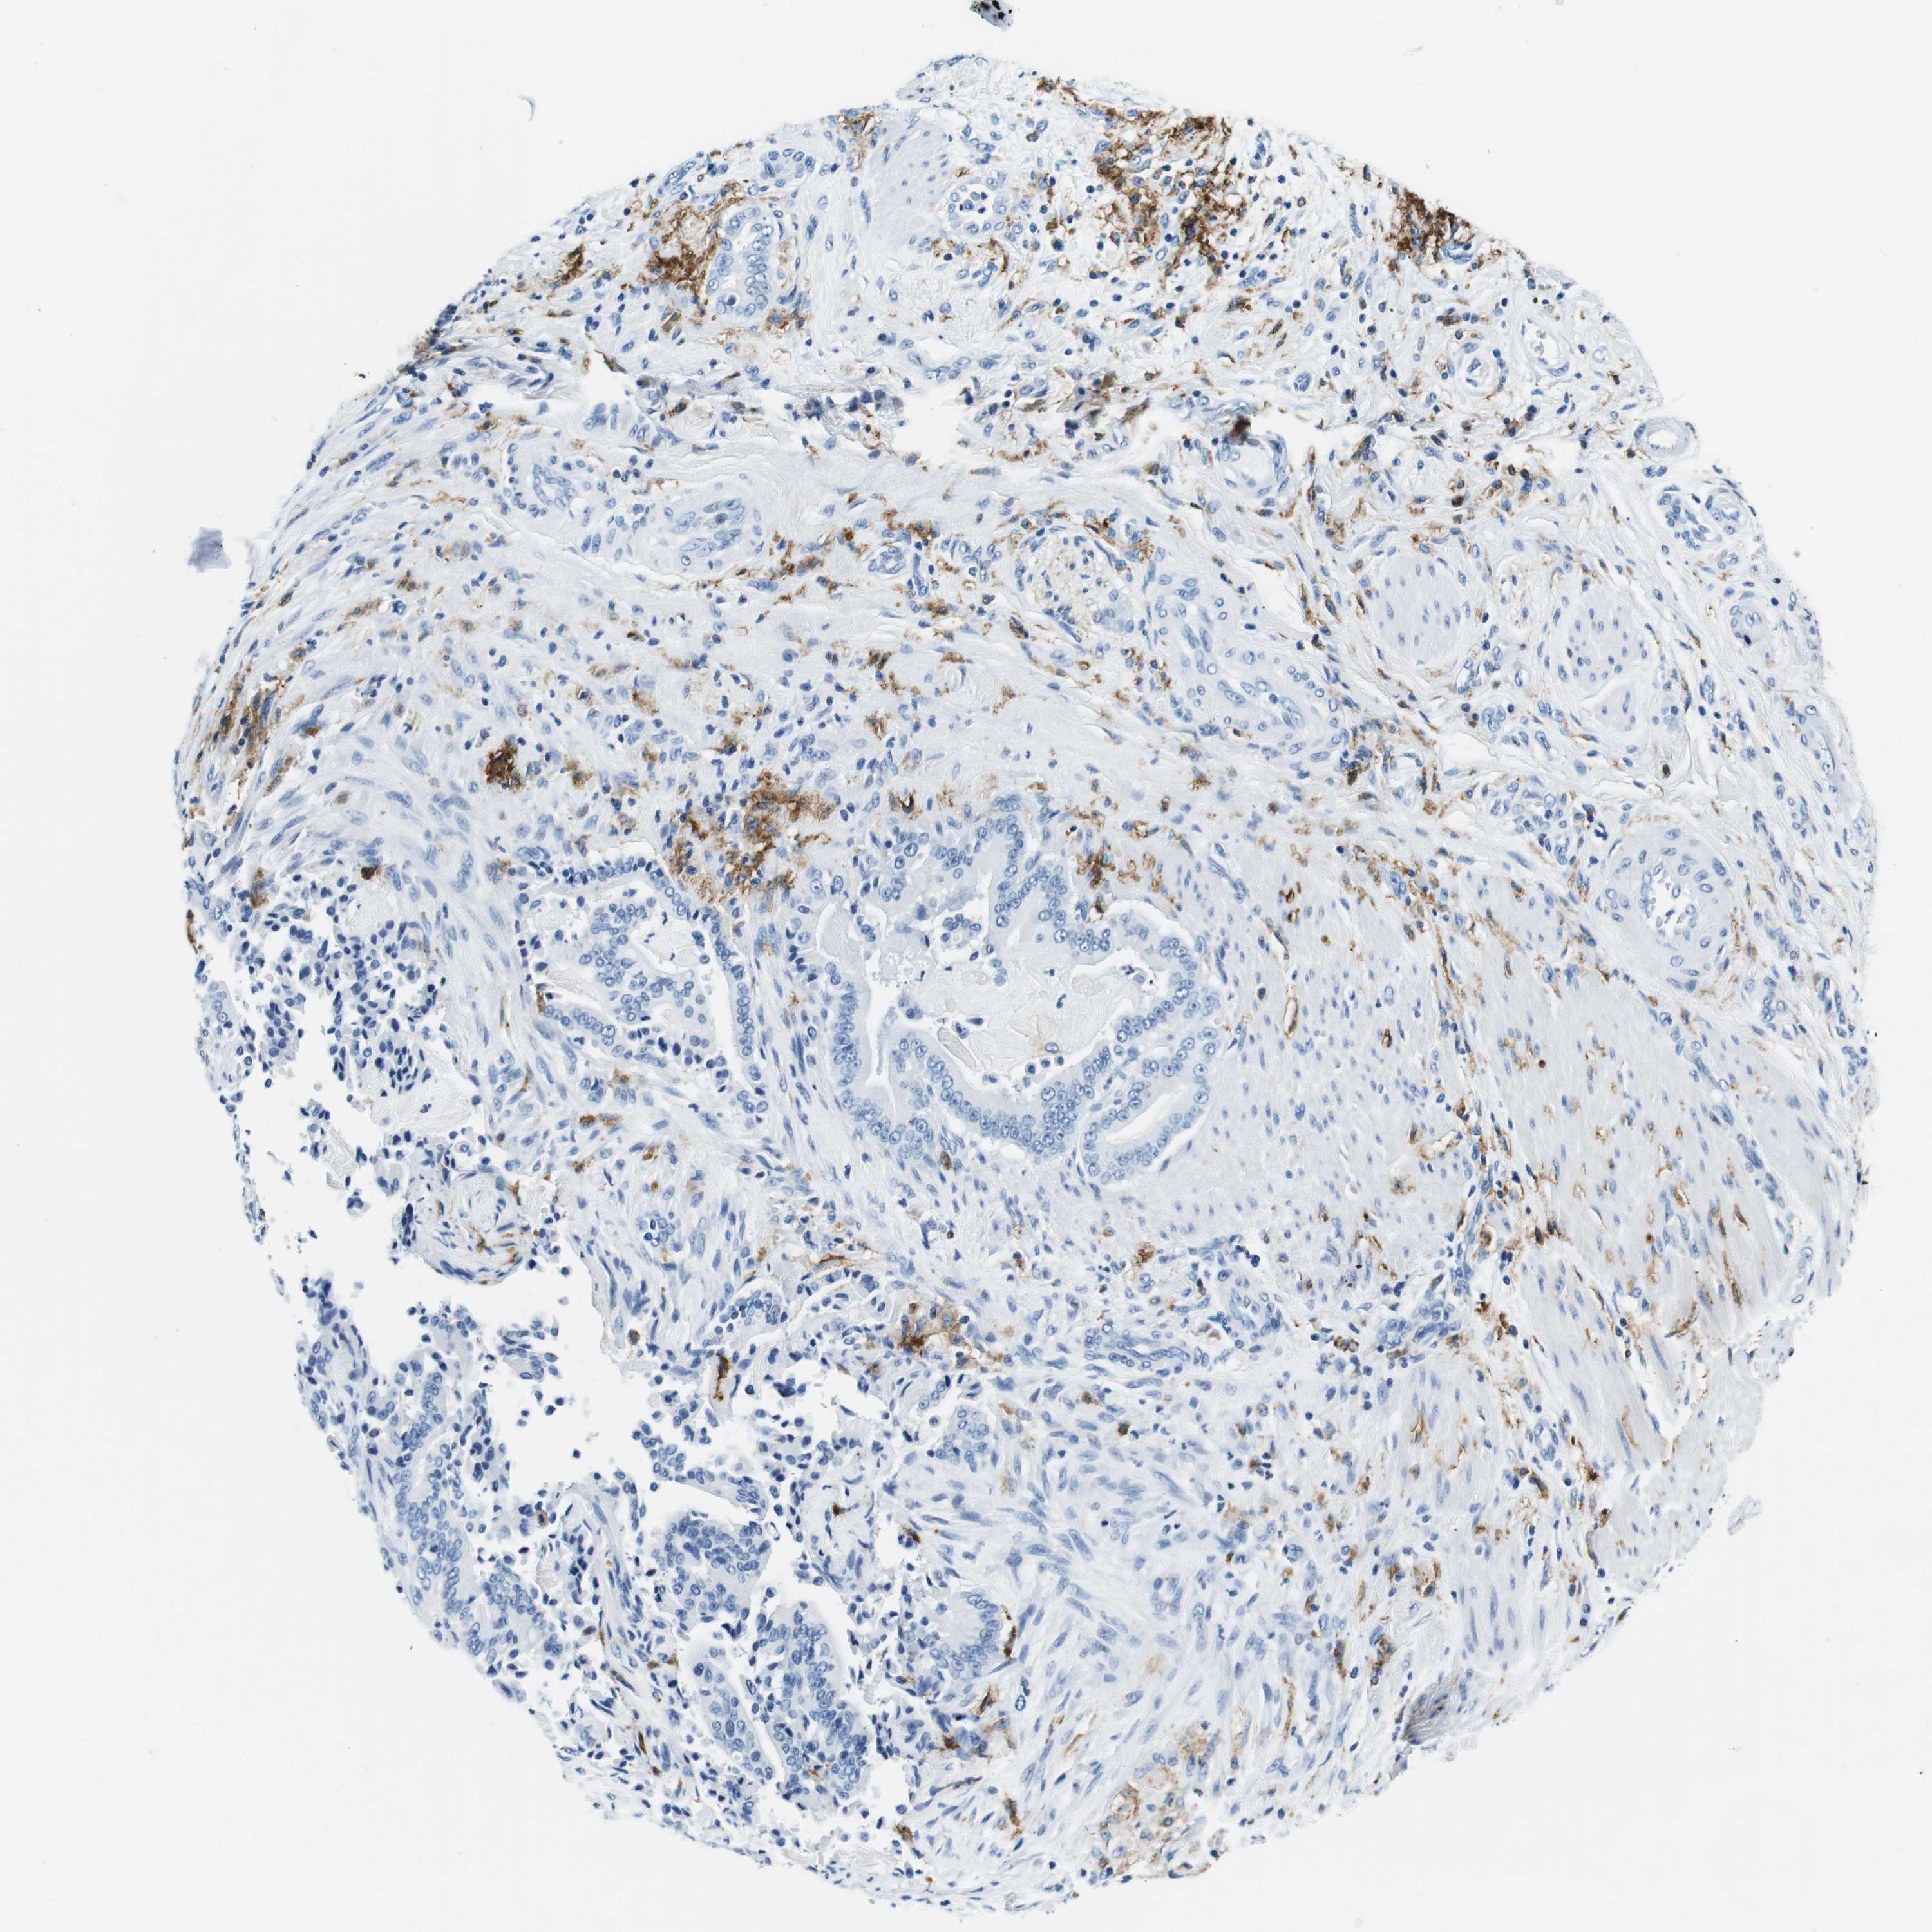

PANCREATIC CANCER - Protein expressioni

A mouse-over function shows sample information and annotation data. Click on an image to view it in a full screen mode. Samples can be filtered based on level of antibody staining by selecting one or several of the following categories: high, medium, low and not detected. The assay and annotation is described here.

Note that samples used for immunohistochemistry by the Human Protein Atlas do not correspond to samples in the TCGA dataset.

Antibody stainingi

Antibody staining in the annotated cell types in the current human tissue is reported as not detected, low, medium, or high, based on conventional immunohistochemistry profiling in selected tissues. This score is based on the combination of the staining intensity and fraction of stained cells.

Each image is clickable and will lead to virtual microscopy that enables deeper exploration of all samples and also displays staining intensity scores, fraction scores and subcellular localization as well as patient and tissue information for each sample.

Antibody HPA043151

Antibody CAB015400

Antibody CAB034021

Staining

High

Medium

Low

Not detected

Intensity

Strong

Moderate

Weak

Negative

Quantity

>75%

75%-25%

<25%

None

Location

Nuclear

Cytoplasmic/membranous

Cytoplasmic/membranous,nuclear

Adenocarcinoma, NOS